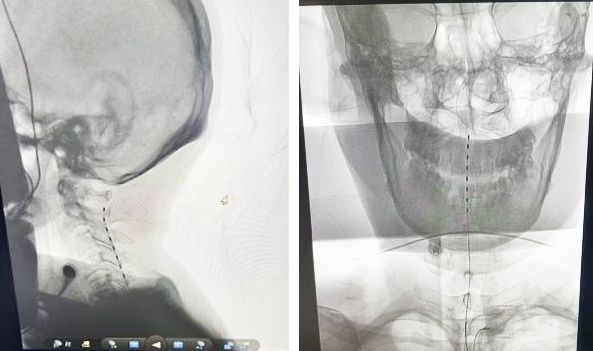

近日,我院神經外科一病區成功獨立完成兩例短時程高頸髓脊髓電刺激促醒術,成為山東省內最早成功開展該技術的單位。

兩個月前,杜女士因一起車禍導致嚴重顱腦損傷、脾臟出血收住我院ICU,經過積極救治生命體征穩定下來,但是轉入普通病房后仍處于昏迷氣管切開狀態。神經外科一病區郝懷勇副主任帶領昏迷促醒團隊,經過科學的評估(CRS-R量表評分、顱腦磁共振、腦電圖、DRS評分、聽覺誘發(ABR)和軀體感覺(SEP)電位),為患者設計了以短時程高位頸髓穿刺電極植入術為主導的個性化綜合促醒方案,該方案得到分管院長于世倫、神經外科李永濤、續繼軍主任的認可和支持。

經過充分術前準備評估后,在介入室、手術室、麻醉科、器械科通力合作下,郝懷勇、葉翔、關家文醫生和介入室盧慶林主任,完成了我院第二例高頸髓脊髓電刺激促醒術。該患者開機第三天在沒有拔除氣管切開管的情況下,已經能夠說出自己名字,并能夠進行短暫的語言交流,目前正在進一步康復中。